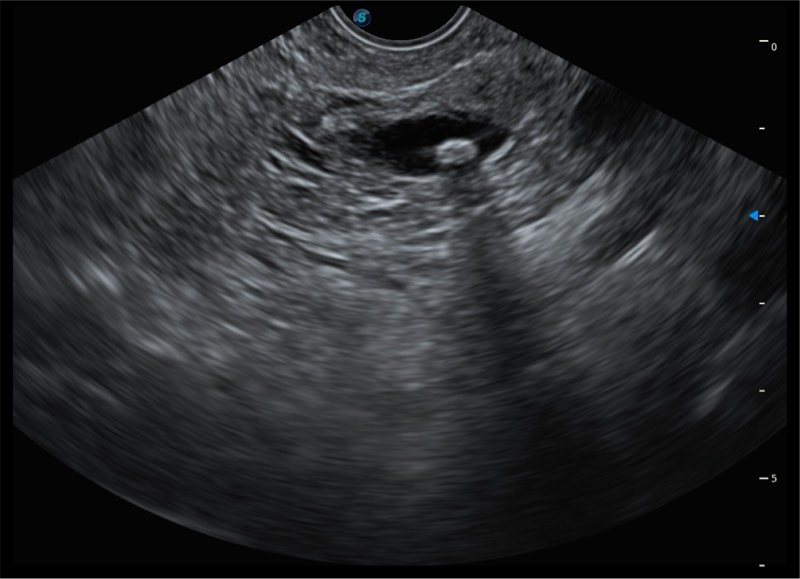

• 搭载百万级CMOS成像技术

• 及自主研发凸阵换能器,

• 可呈现优质的内镜和超声画面

基于二十年的超声技术积累,乐玩lewin国际提供了最新一代的独立超声主机,在提供高质量图像的同时满足多学科使用。具备常见多普勒技术并提供弹性成像、声学造影等高端影像技术。新一代传感器具有更强的抗干扰能力并减少图像伪影。

• 4-12MHZ宽频输出